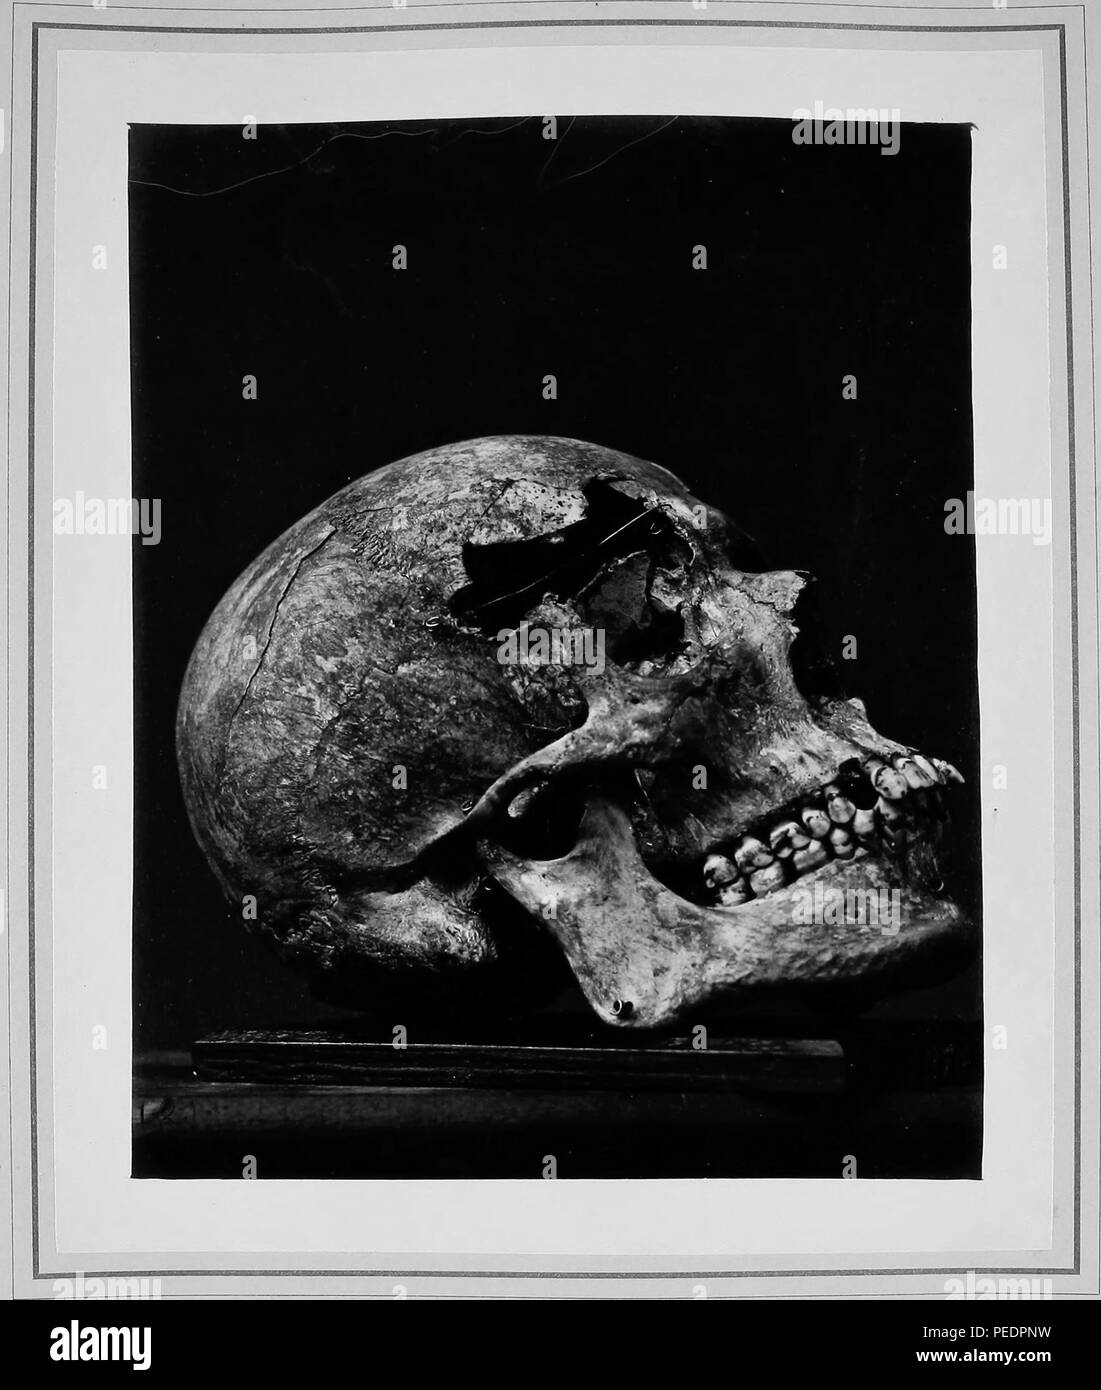

Black and white photograph showing the fractured cranium of Private Edward Volk, who was wounded August 30, 1862, at the second battle of Bull Run, by a musket ball, which struck his forehead half an inch above the right eyebrow, 1865. Courtesy Internet Archive. () Stock Photohttps://www.alamy.com/image-license-details/?v=1https://www.alamy.com/black-and-white-photograph-showing-the-fractured-cranium-of-private-edward-volk-who-was-wounded-august-30-1862-at-the-second-battle-of-bull-run-by-a-musket-ball-which-struck-his-forehead-half-an-inch-above-the-right-eyebrow-1865-courtesy-internet-archive-image215432837.html

Black and white photograph showing the fractured cranium of Private Edward Volk, who was wounded August 30, 1862, at the second battle of Bull Run, by a musket ball, which struck his forehead half an inch above the right eyebrow, 1865. Courtesy Internet Archive. () Stock Photohttps://www.alamy.com/image-license-details/?v=1https://www.alamy.com/black-and-white-photograph-showing-the-fractured-cranium-of-private-edward-volk-who-was-wounded-august-30-1862-at-the-second-battle-of-bull-run-by-a-musket-ball-which-struck-his-forehead-half-an-inch-above-the-right-eyebrow-1865-courtesy-internet-archive-image215432837.htmlRMPEDPNW–Black and white photograph showing the fractured cranium of Private Edward Volk, who was wounded August 30, 1862, at the second battle of Bull Run, by a musket ball, which struck his forehead half an inch above the right eyebrow, 1865. Courtesy Internet Archive. ()